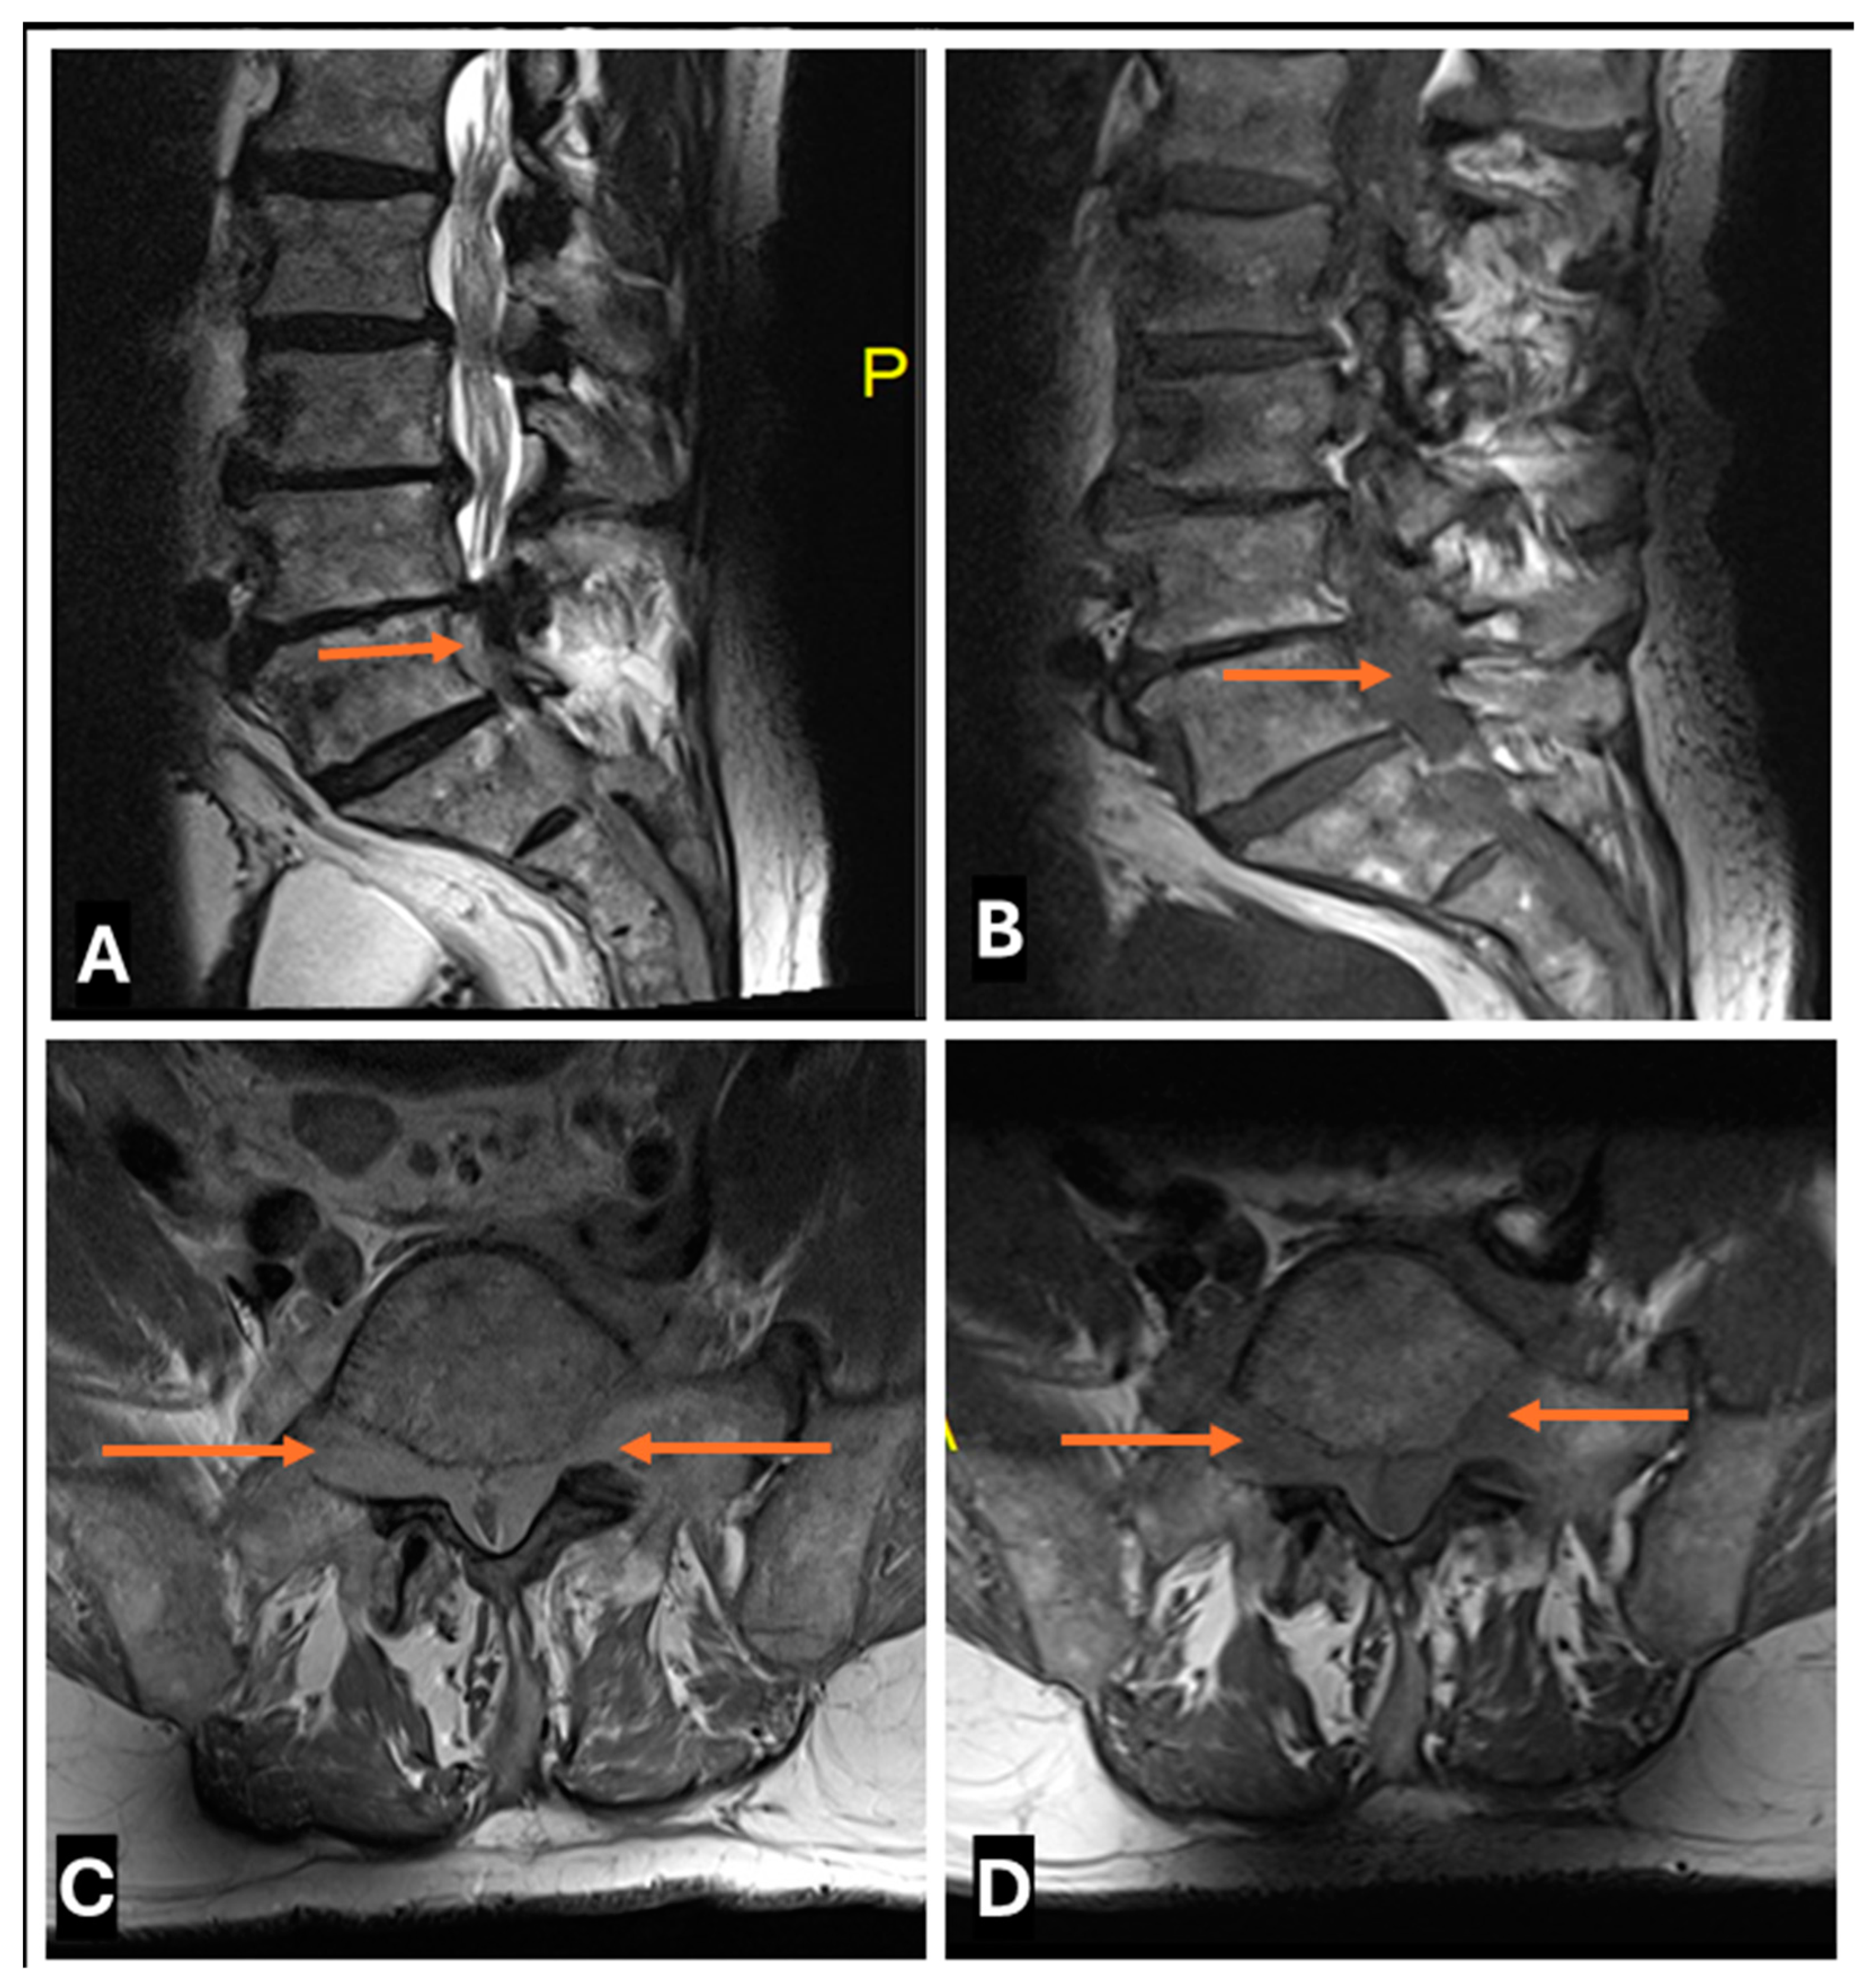

- Primary Sarcomas: Soft-tissue sarcomas are uncommon, accounting for just over 1% of adult malignancies. Synovial sarcoma, clear cell sarcoma, and epithelioid sarcomas are known to involve peripheral nerves. CT/MR reveals a large soft tissue mass with areas of necrosis or calcification and heterogeneous contrast enhancement. F-18 FDG uptake is useful for both tumor staging and treatment assessment (Figure 26, Figure 27 and Figure 28).